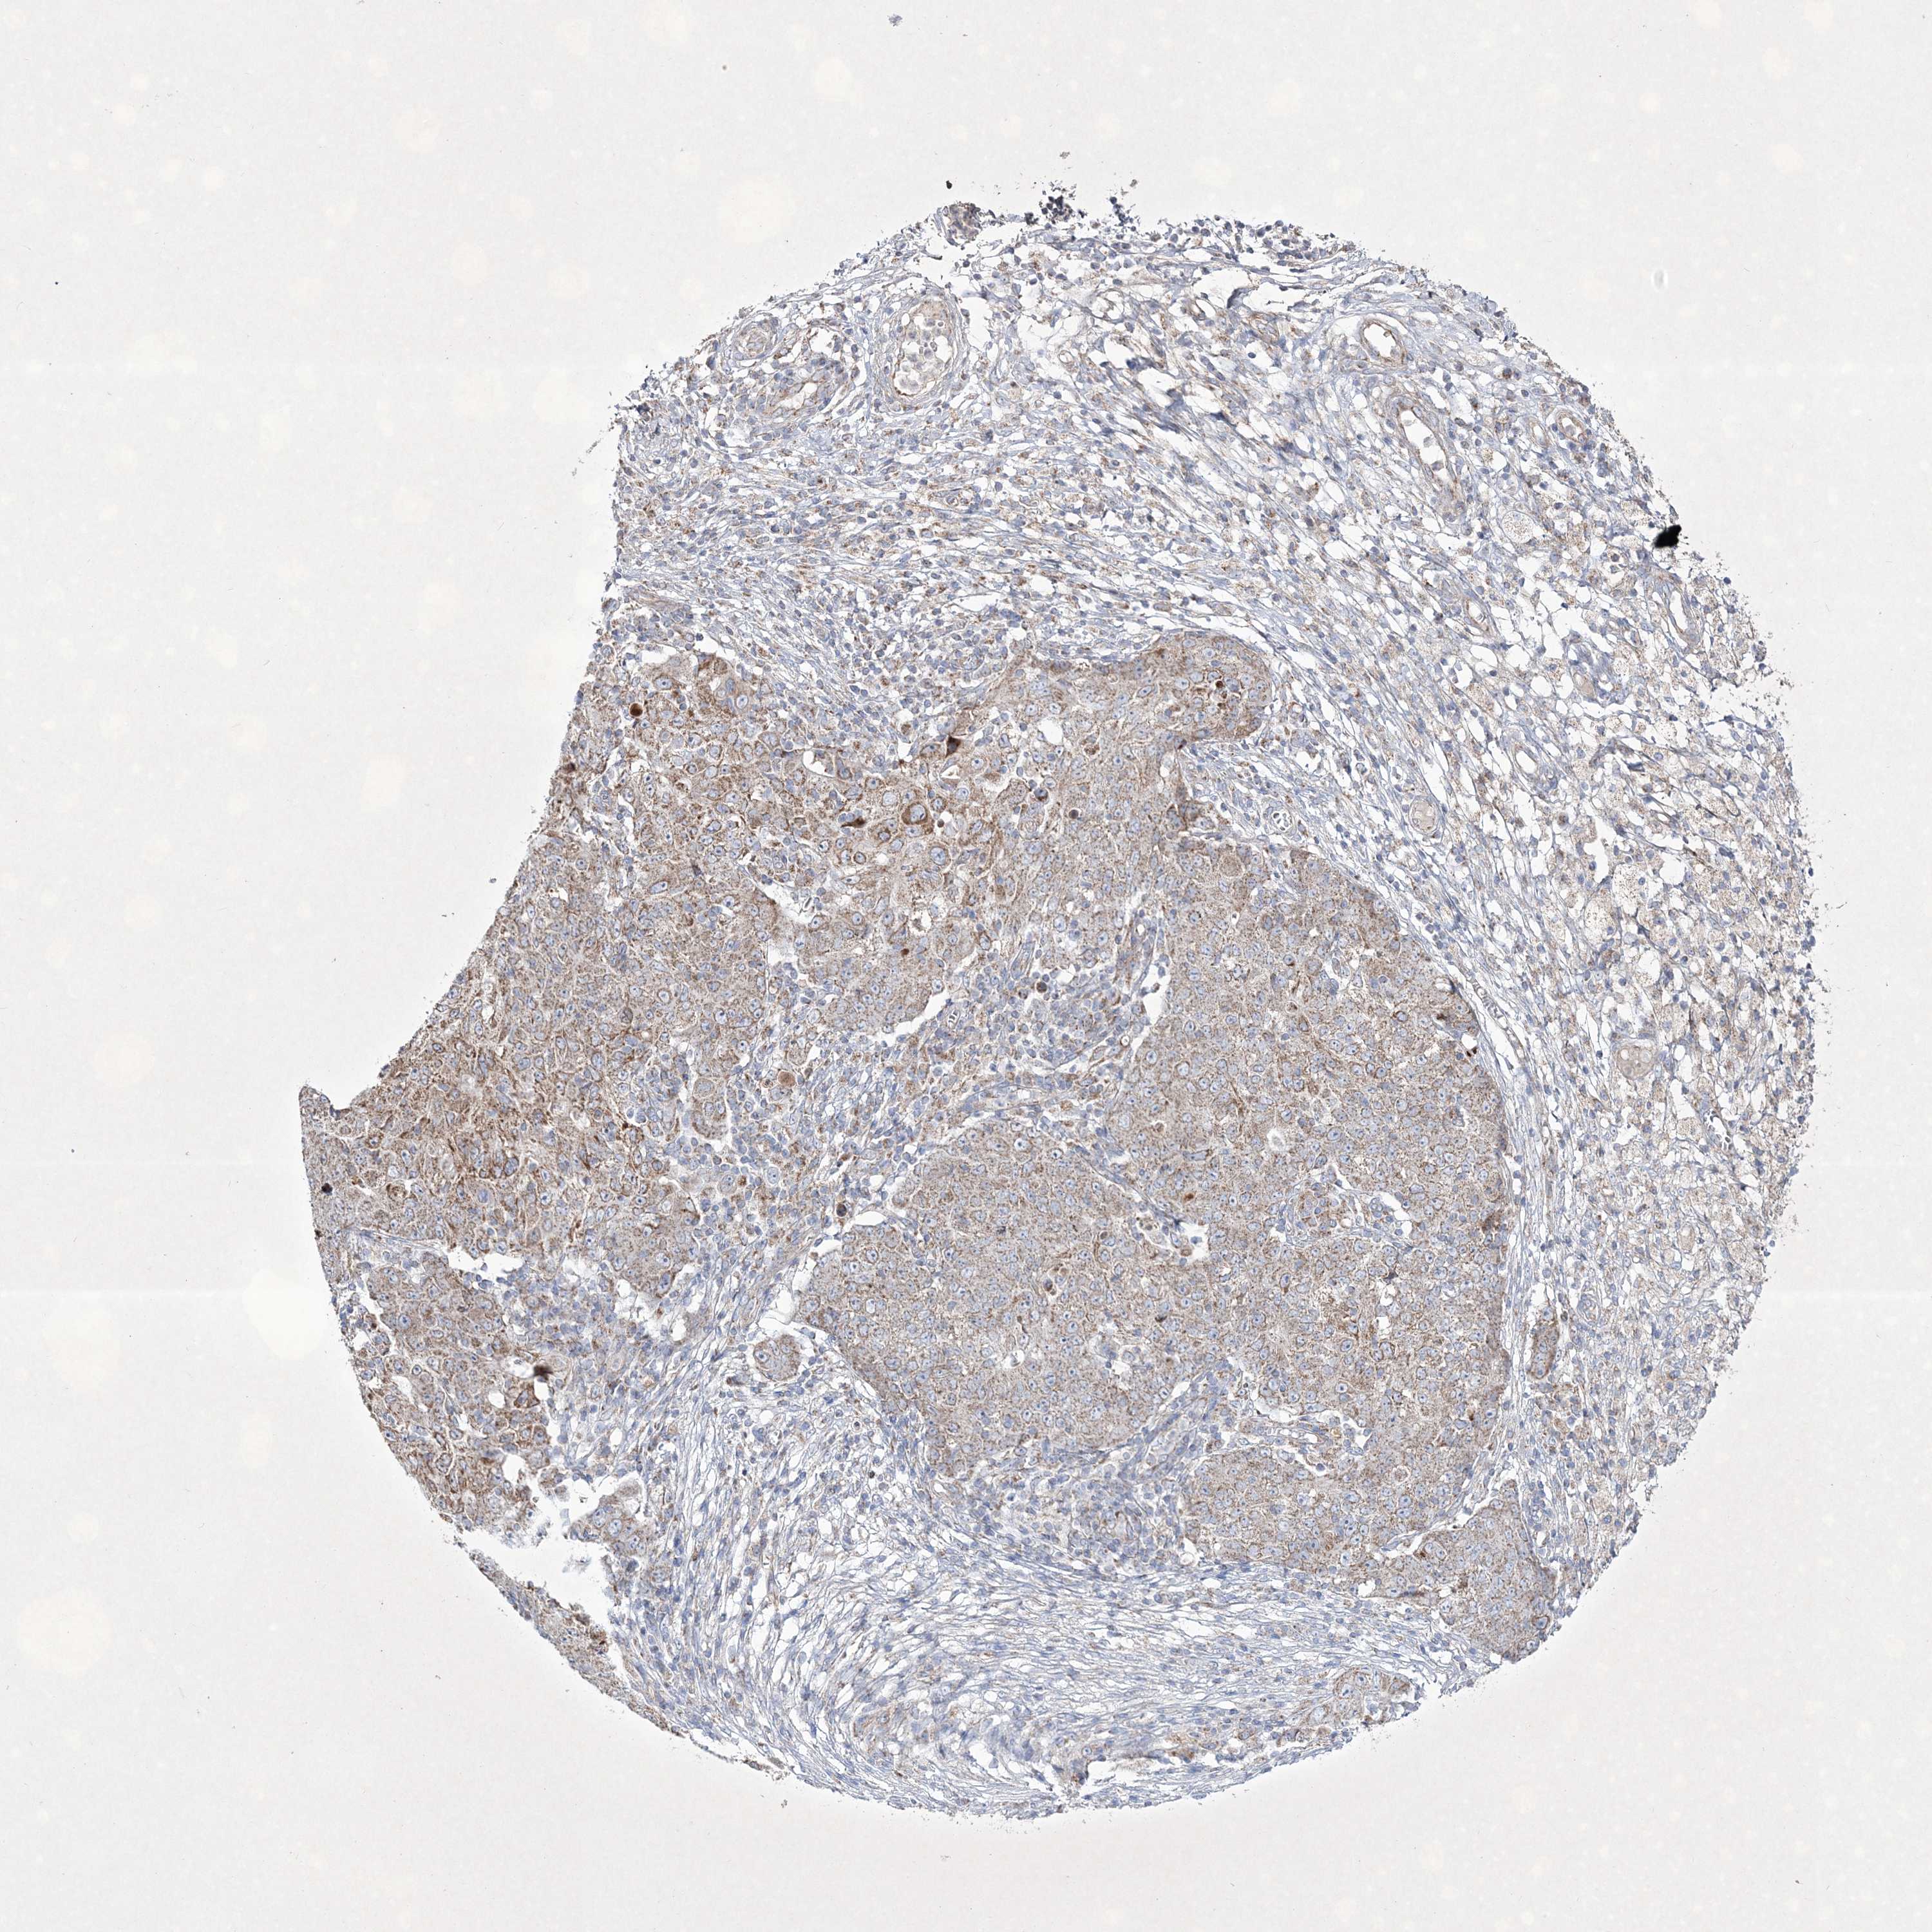

OVARIAN CANCER - Protein expressioni

A mouse-over function shows sample information and annotation data. Click on an image to view it in a full screen mode. Samples can be filtered based on level of antibody staining by selecting one or several of the following categories: high, medium, low and not detected. The assay and annotation is described here.

Note that samples used for immunohistochemistry by the Human Protein Atlas do not correspond to samples in the TCGA dataset.

Antibody stainingi

Antibody staining in the annotated cell types in the current human tissue is reported as not detected, low, medium, or high, based on conventional immunohistochemistry profiling in selected tissues. This score is based on the combination of the staining intensity and fraction of stained cells.

Each image is clickable and will lead to virtual microscopy that enables deeper exploration of all samples and also displays staining intensity scores, fraction scores and subcellular localization as well as patient and tissue information for each sample.

Antibody HPA037802

Antibody HPA037803

Staining

High

Medium

Low

Not detected

Intensity

Strong

Moderate

Weak

Negative

Quantity

>75%

75%-25%

<25%

None

Location

Nuclear

Cytoplasmic/membranous

Cytoplasmic/membranous,nuclear

Cystadenocarcinoma, serous, NOS